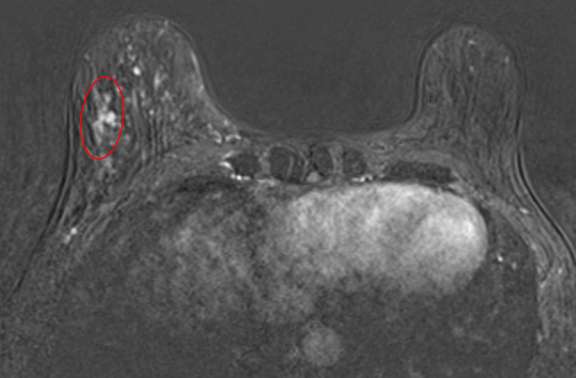

The combination of NME distribution and internal enhancement pattern with other morphologic MRI features and contrast kinetic curves (discussed separately) can help differentiate findings that are more or less suspicious for malignancy, but often NME findings ultimately require MRI-guided core needle biopsy for definitive diagnosis.4 Figures 1 through 3 demonstrate examples of biopsy-proven malignant NME.